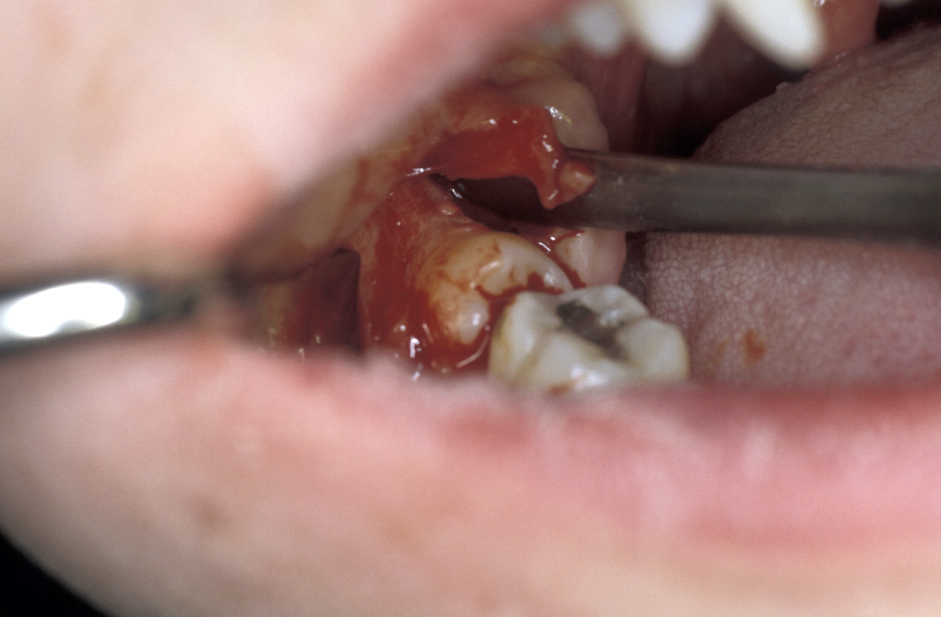

- Bone removal – this is usually done with either a burr (Figure 6) or (rarely now) chisels. A piezoelectric saw has been used but much less commonly. How much bone needs to be removed depends on the position of the tooth. Care is required to ensure that enough bone remains to support the second molar tooth. If chisels are used, mesial and distal stop cuts need to be placed to prevent fracture propagation (Figure 7).

- Tooth removal – in less impacted cases a point of application may be drilled into the tooth, which is then elevated out of the socket (Figure 8). It is important not to lever the tooth out as any resistance may change the fulcrum of elevation and result in the inferior dental nerve being crushed. If the tooth does not elevate it may be better to divide it and remove it in pieces. This is where the unprotected lingual nerve may be damaged if the burr is passed too deeply.